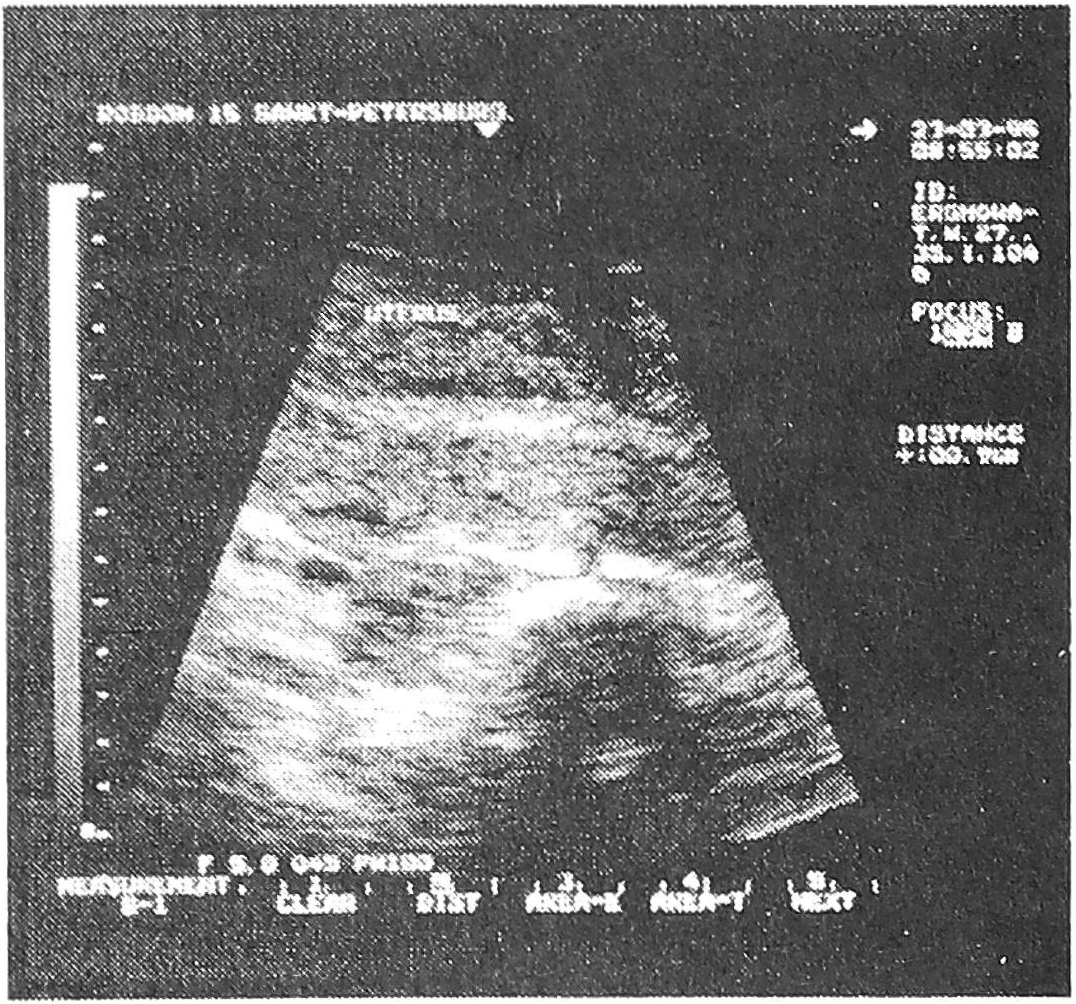

На эхограмме (рис. 6) при продольном сканировании виден инфильтрат в области послеоперационного рубца на матке.

Рис. 6. Инфильтрат послеоперационного рубца.

Образование имеет четкий контур, размеры 78 х 53 мм и неоднородную эхоструктуру.